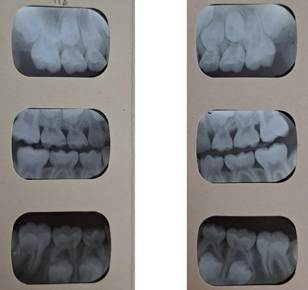

Radiografías

Las radiografías periapicales y la panorámica mostraron un desarrollo dental de un paciente de 7 años. (Fig. 10, 11 y 12)

Fig.

11

Rx periapicales incisivos Fig. 12 Rx

periapicales molares y de mordida